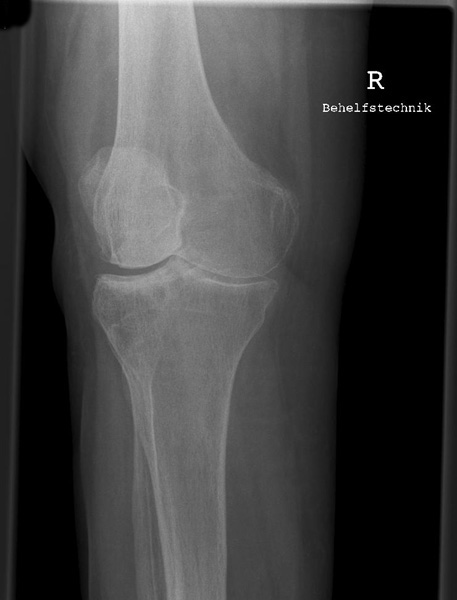

Knie a.p.

Fehler

Die Patella ragt über die laterale Begrenzung des distalen Femur hinaus, gleichzeitig projiziert sich das ganze Fibularköpfchen in dem Tibiakopf. Überdies wird dann das Tuberculum intercondylare mediale von der medialen Gelenkrolle des Femus verschattet. Bei dieser Fehleinstellung lassen sich z.B. posttraumatische Verkalkungen, die medial am inneren Gelenkknorren des Oberschenkels liegen (sog. Stieda-Pellegrinische Schatten), nicht mehr erkannt werden.

Abhilfe

Der nach außen schauende Fuß muss leicht, also nicht zu stark, nach innen gedreht werden, Großzehenwärts.